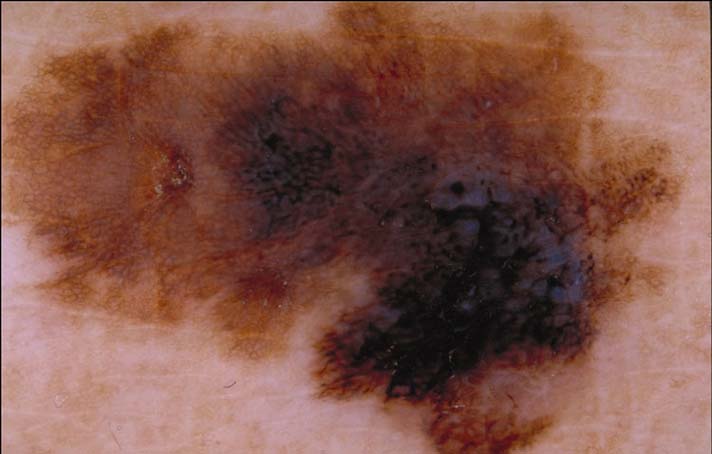

| 120 "diagnosis.char"="Melanocytic lesion" "comment.char"="" "features.char"="Aggregated brown or black globules|Pigment network - pseudonetwork (see exception 1)|Pseudopods or Radial Streaming (circumferential or focally present)" | "diagnosis.char"="Invasive Melanoma, Breslow 0.8mm" "breslow_depth.float"="0.8" "comment.char"="" "features.char"="Blue-white veil|Broadened network|Multiple (5-6) colors|Peripheral black dots/globules|Pseudopods" |  |  |